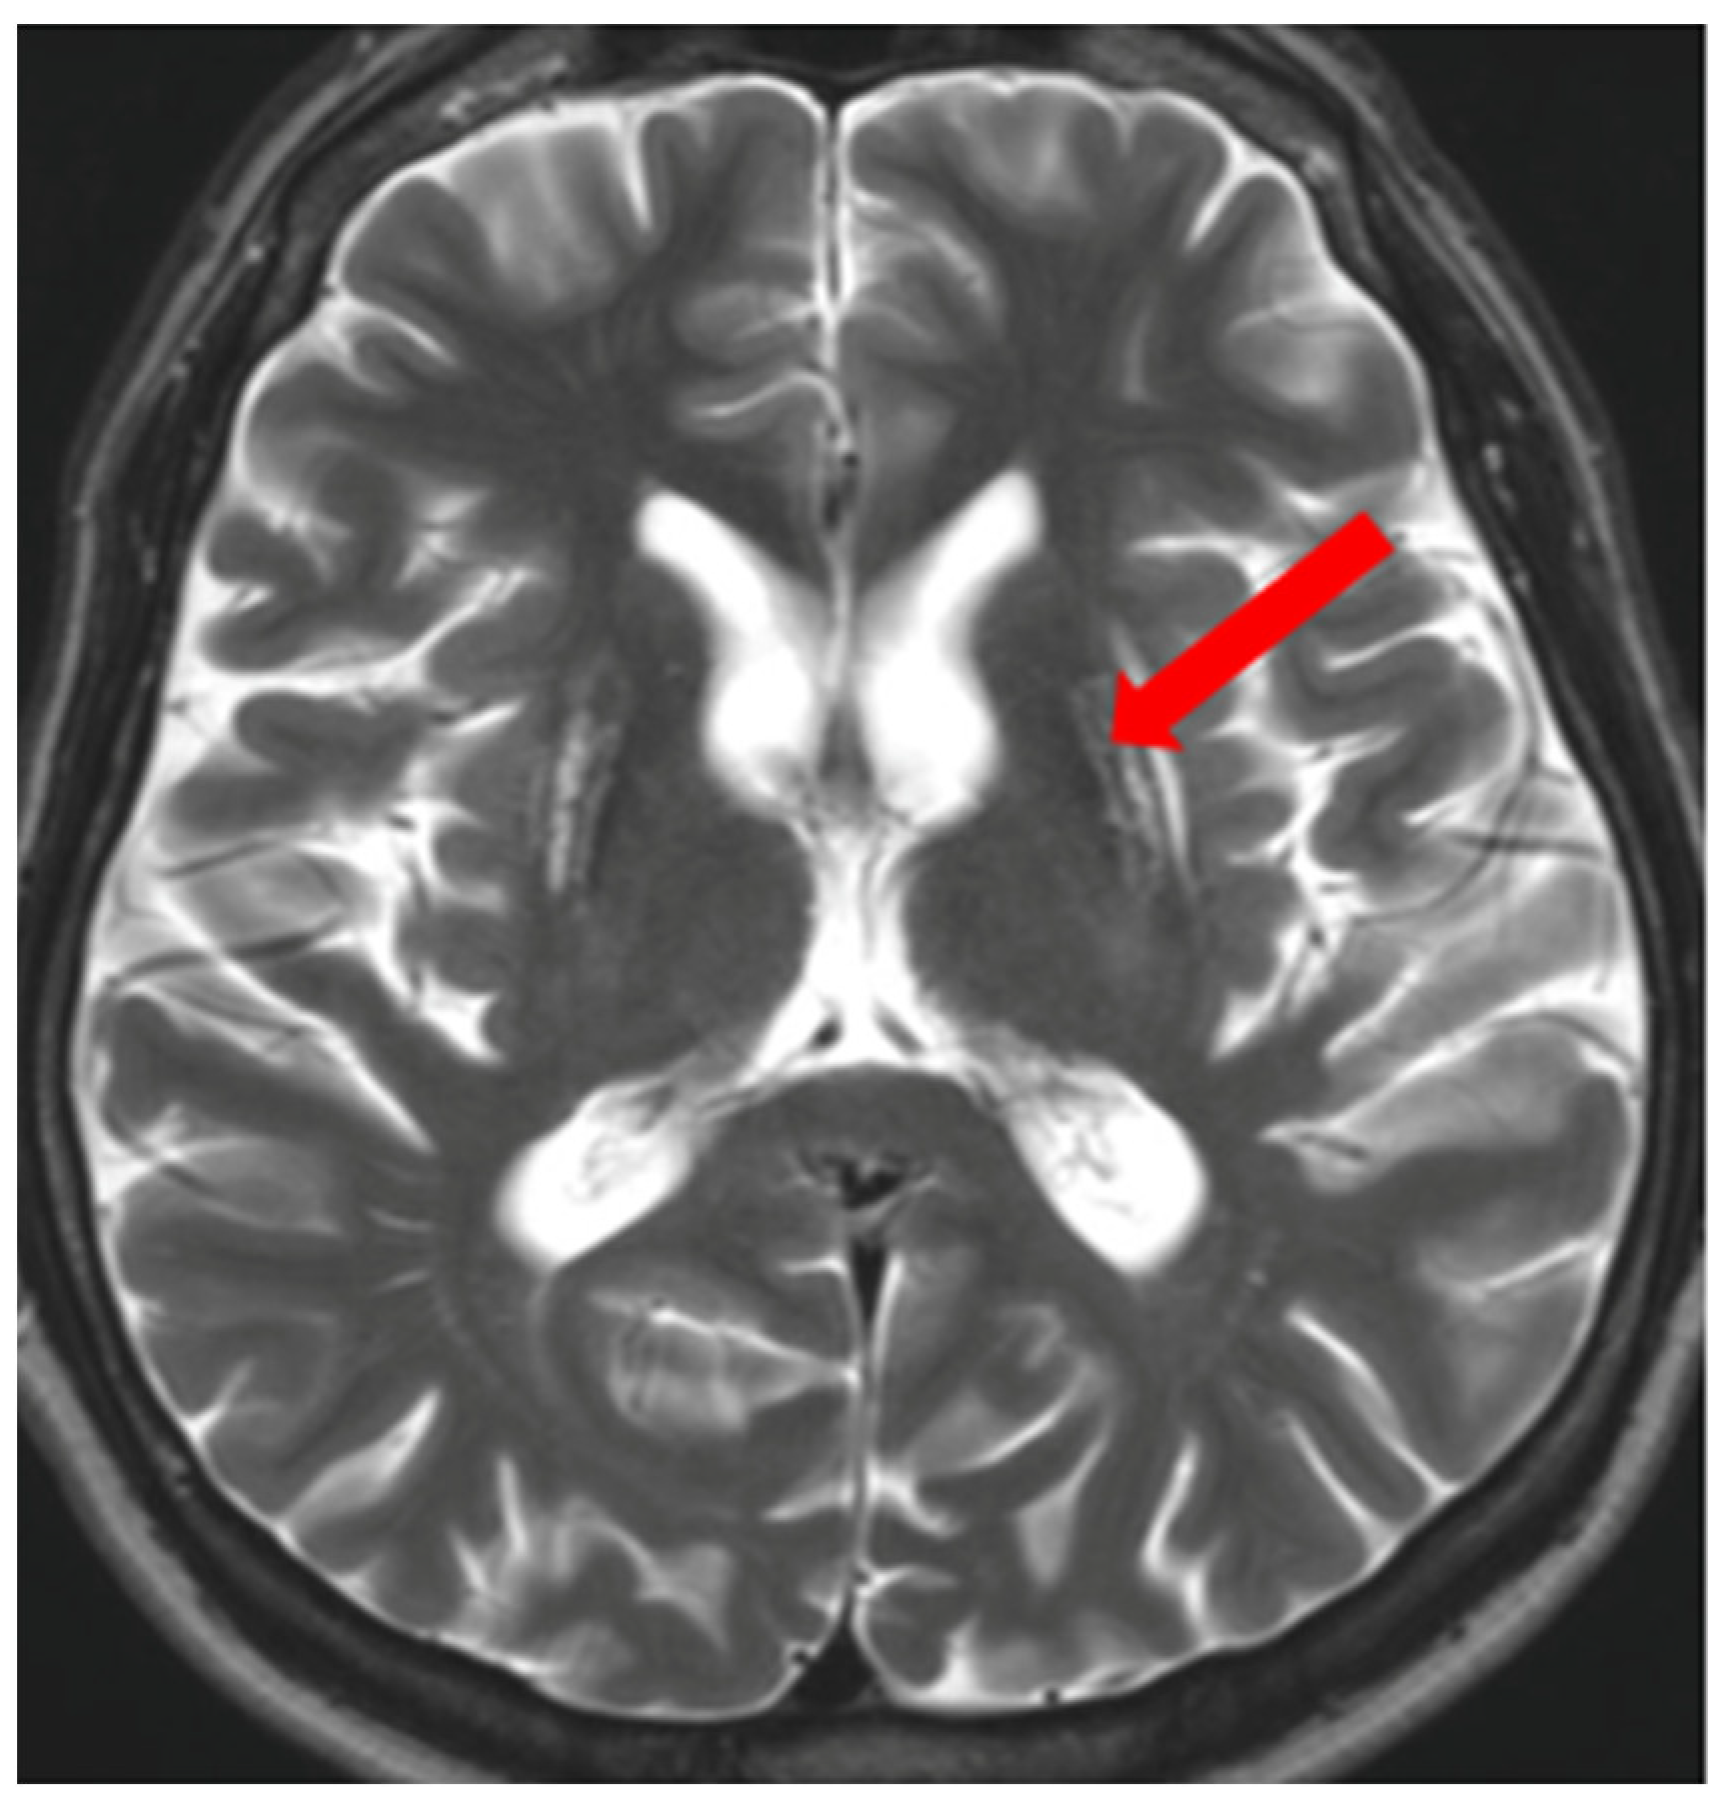

3.1. Classical Brain MRI Examination in WD Patients

5. Neuroradiological Pathognomonic Signs of WD